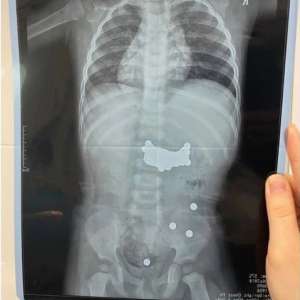

Игры с конструктором довели до реанимации: годовалый малыш проглотил 390 магнитов

В Дагестане медики провели срочную операцию ребенку, проглотившему почти 400 магнитных шариков.

Врачи призывают родителей быть осторожнее с игрушками.